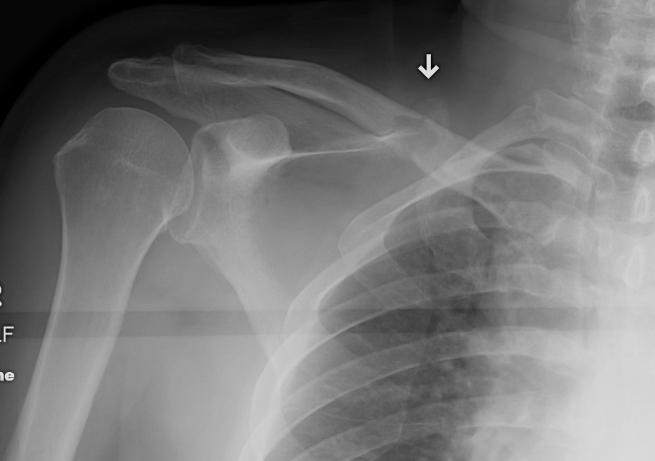

X-ray

Bone involved

Any other bones with pain

CXR